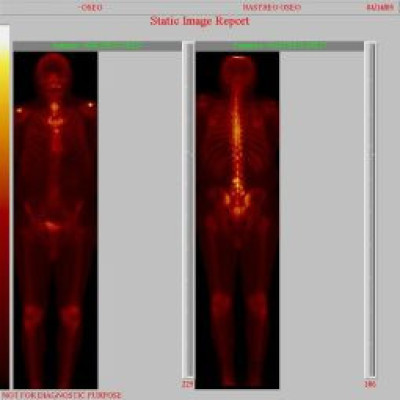

Metástasis óseas por cáncer de prostata

Envíado por Instituto Nacional de Cardiología y Cirugía Cardiovascular